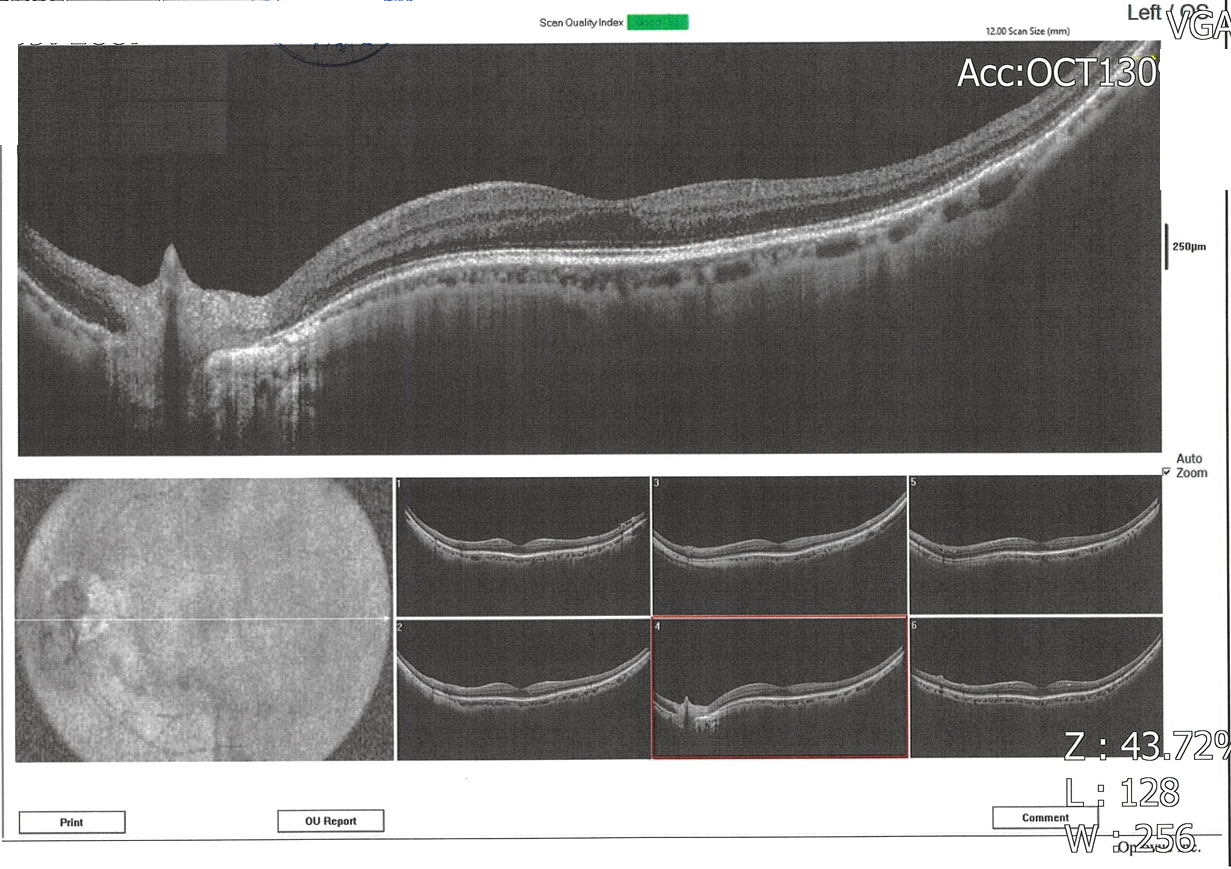

因為左眼在暗處往左看會出現垂直閃光而前往醫院就診,麻煩版主幫忙看一下報告,請問確定是青光眼?嚴重程度?

雙眼杯盤比及視網膜厚度大致正常,但左眼視野敏感度似乎整體性的下降,通常這和白內障比較有關,火勢其他問題,青光眼不會有閃光現象,所以要讓醫師檢查一下眼底,看有沒有視網膜剝離或裂孔,如果你接近50歲左右,也有可能是玻璃體老化液化而拉扯到視網膜,產生閃光